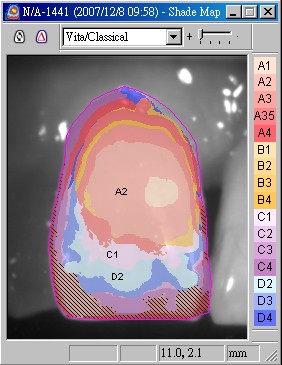

經過3個月後,由於骨整合完全,準備製作假牙,雖然是後牙區,但假牙的顏色仍相當重要,因此使用數位比色(圖七)及數位攝影(圖八),取得牙齒之精確顏色分佈。

圖七 |